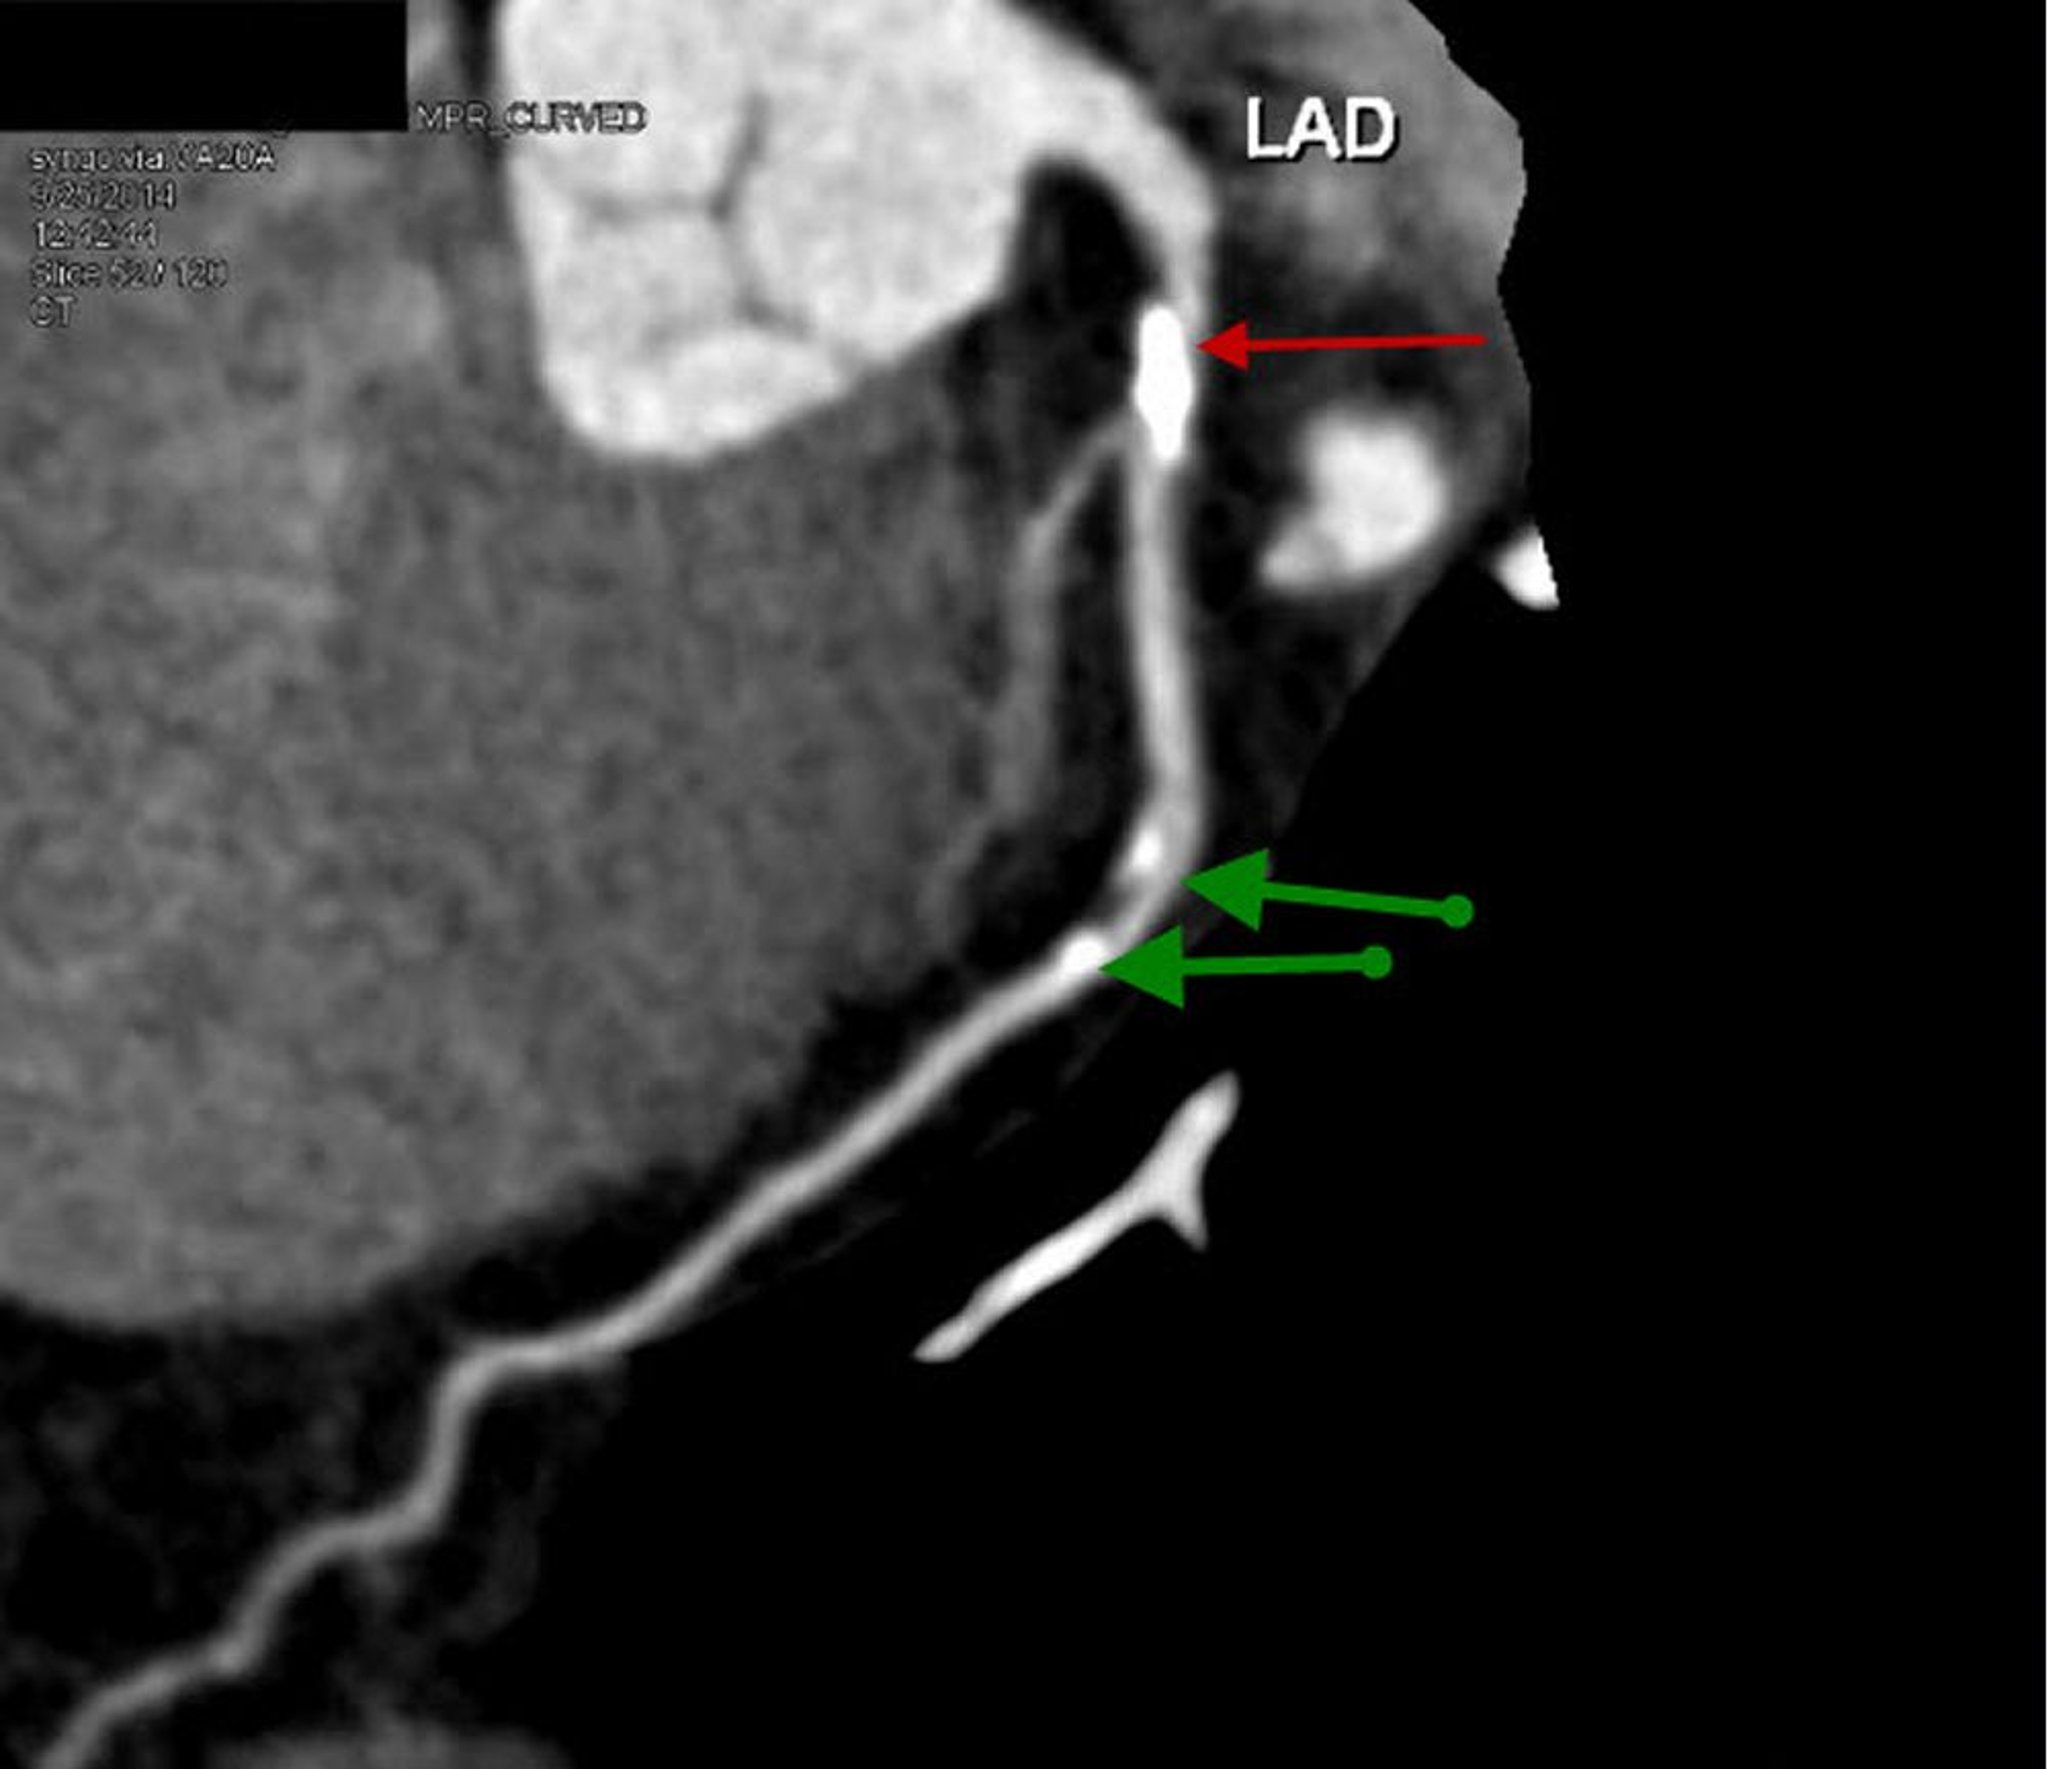

TDM avec contraste montrant une maladie des artères coronaires

Cette TDM avec contraste montre une incidence sagittale reconstruite de l'interventriculaire antérieure gauche proximale avec une plaque calcifiée proéminente et une sténose à 70% (flèche rouge). L'artère interventriculaire antérieure présente une sténose légère de 20 à 30% (flèches vertes).